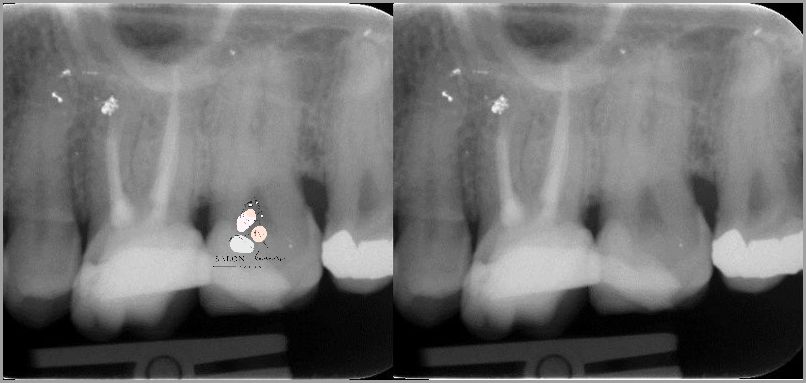

Jeśli masz ból zęba po leczeniu kanałowym, należy skontaktować się z lekarzem stomatologiem w celu ustalenia przyczyny. Lekarz może zlecić zdjęcie RTG, aby zobaczyć, czy ząb jest w dobrym stanie. W przypadku wykrycia problemu lekarz może zalecić dodatkowe leczenie, aby wyeliminować ból. Możliwe jest również zastosowanie znieczulenia lub innych metod łagodzenia bólu.